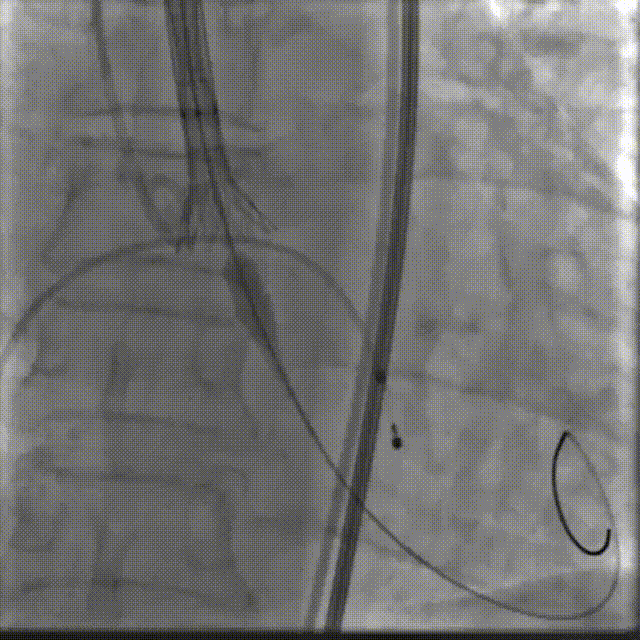

手术影像

主动脉根部造影

18mm球囊预扩

球扩后瓣膜开始定位

工作位造影:位置理想

最终造影:位置理想,形态良好,无漏

撤出大鞘